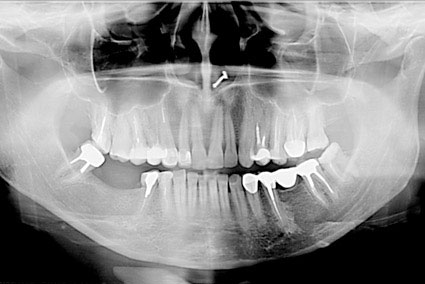

Ортопантомограф - це стоматологічний рентген

апарат для отримання панорамних зображень щелепної зони і суглобів щелепи. Його

головне достоїнство полягає в тому, що знімок ортопантомографа показує

одночасно обидві щелепи і всі зуби. У цьому його принципова відмінність від

прицільної рентгенівської зйомки.

На сьогоднішній день два типи ортопантомографів представлені в продажу: цифрові і плівкові.

Найбільш повну інформацію несуть панорамні знімки. Для отримання панорамного знімка випромінювач (рентген-трубка) і приймач (рентген-плівка або цифровий напівпровідниковий датчик) рухаються навколо голови пацієнта по певній траєкторії.